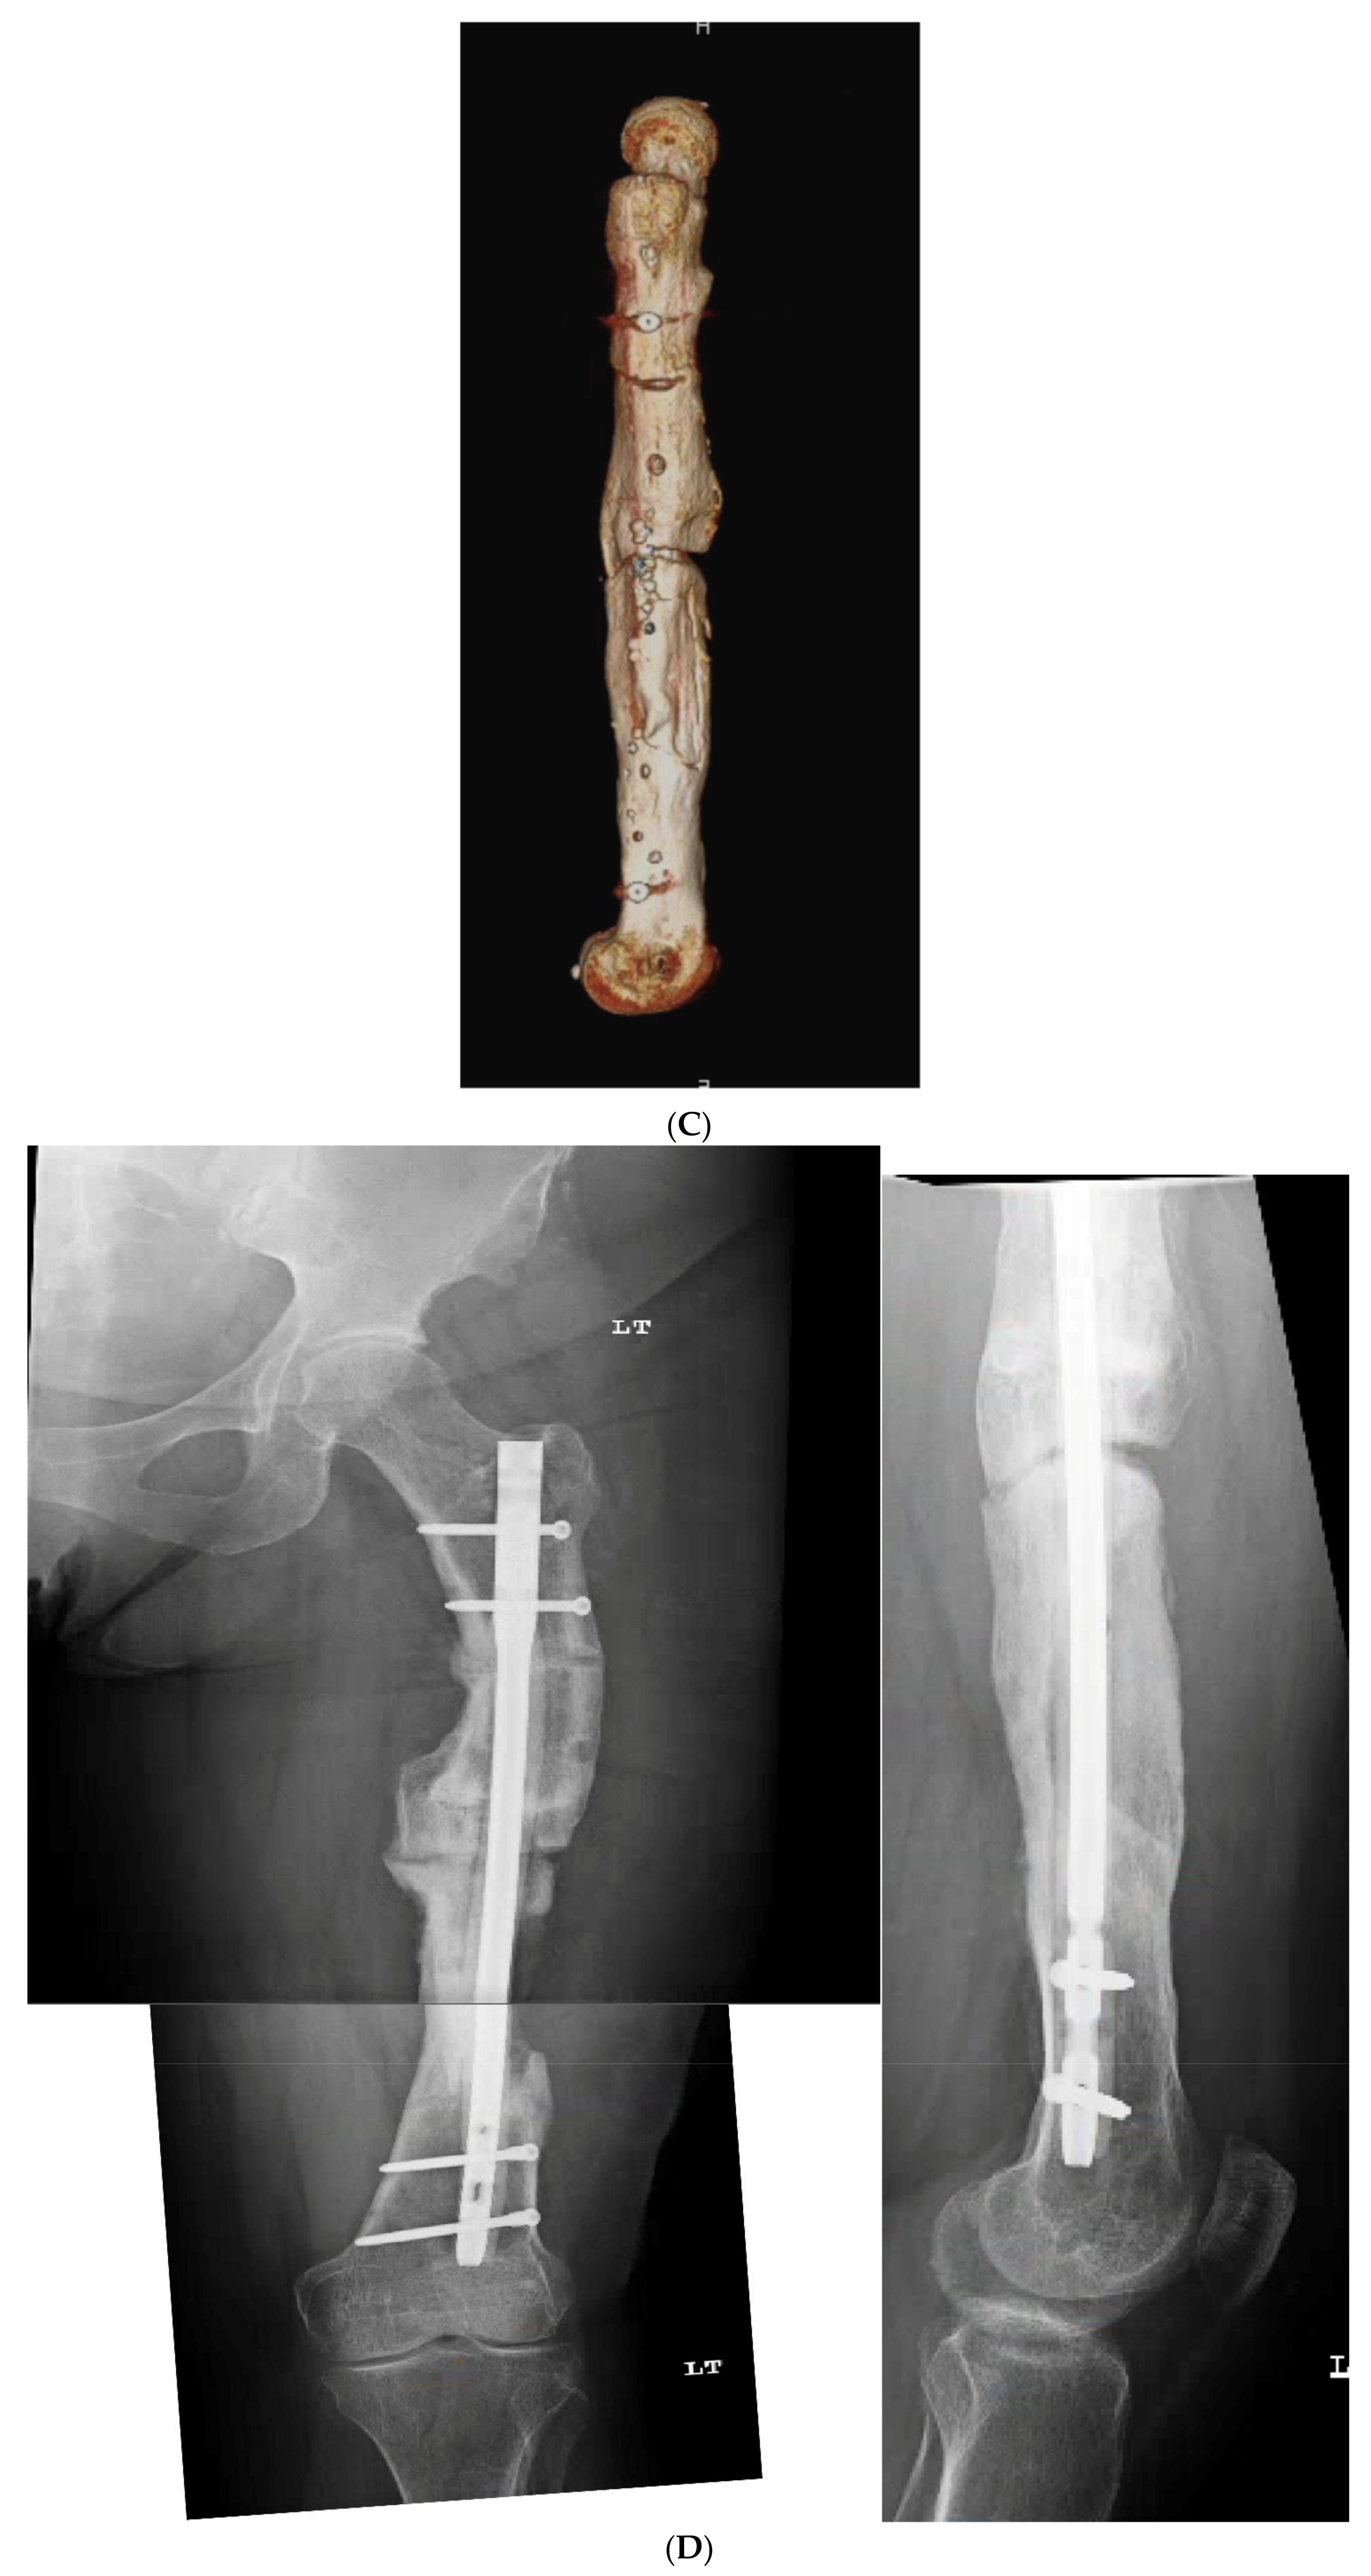

3.3. Case 3-Single-Plane Correction with Nail: Tibia

An adult male with no comorbidities presented with varus malunion following intramedullary tibial nailing, reporting symptomatic medial knee pain (Figure 8A). The CORA analysis revealed a varus deformity of 12 degrees. With a deformity in the coronal plane, surgical access was through an anterior approach using a focal dome osteotomy for correction. The anterior compartment was elevated, and a drill bit was placed in the CORA, with a parallel drill guide used to draw the arc with a second drill bit. The osteotomy was completed with an osteotome. The alignment was maintained during reaming using a temporary plate (Figure 8B). The patient underwent compression nailing using a magnetic motorized nail, allowing for subsequent compression as needed after discharge (Figure 8C). The patient felt pain-free at 12 weeks, yet was encouraged to return for regular follow-up examinations and X-rays until radiographic healing. Patient lost to follow-up after 6 months (Figure 8D).

Figure 8.

(A) Adult male with varus malunion deformity after a prior tibia fracture and nailing. (B,C) Patient underwent focal dome osteotomy with compression nailing using a magnetic motorized nail for early and subsequent nail compression. (D) Patient declined to follow-up after 12 weeks, citing absence of pain. Patient returned at 6 months at request of surgeon, still without pain. Magnetic nail recompressed. Patient lost to follow-up after 6 months.